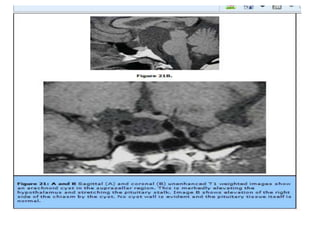

Right para-sellar arachnoid cyst.

Intra-sellar arachnoidal cyst resulting in an “empty-sella” (coronal and sagittal

imaging). No displacement of the stalk.